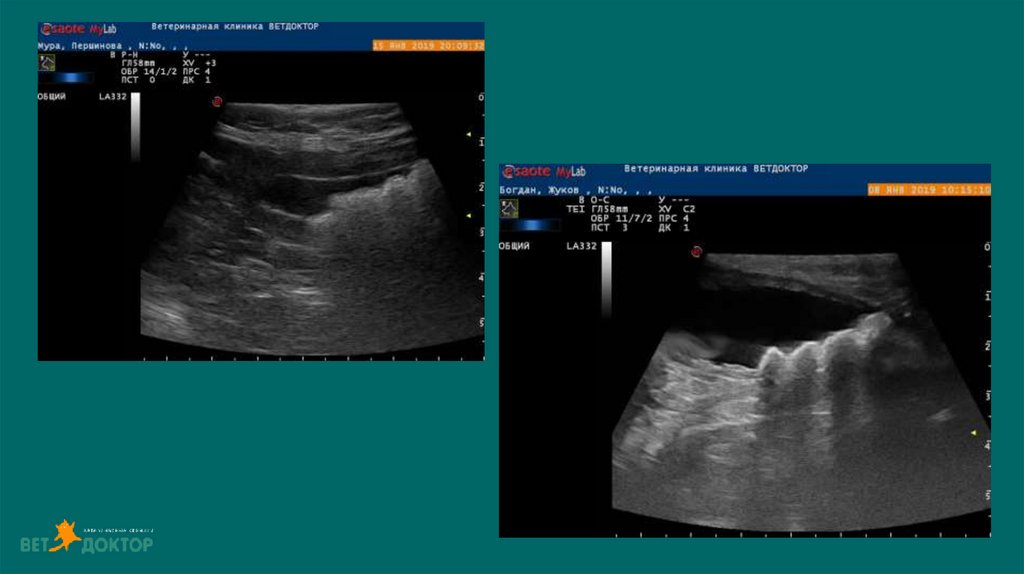

38. УЗИ

Дилатация лоханки более 13 мм - обструкция

При диаметре лоханки более 8мм-высокая

вероятность обструкции

39. Клиническое значение расширения лоханки при УЗИ у кошек/собак

УЗИ 81 собаки и 66 кошек с раширением лоханки.

Было сформировано 6 групп:

1.Клинически нормальная функция почек;

2.Клинически нормальная функция почек при диурезе;

3.Пиелонефриты;

4. Неинфекционной почечной недостаточностью;

5. Обструкция выносящего тракта;

6.Смешанные необструктивные аномалии

Ширина лоханки в 1 группе была ниже, чем в 3-5 группах (среднее значение 2 мм у собак и 1.6 мм у

кошек), но не было

специфичной разницы от группы 2

во 2 группе среднее значение 2.5 у собак и 2.3 у кошек

в 3 группе - 3.6 мм и 4 мм соответственно

в 4 группе - 3.1 мм и 2.8 мм

в 5 группе - 15.1 мм и 6.8 мм

в 6 группе – 3.8 мм и 3.0 мм